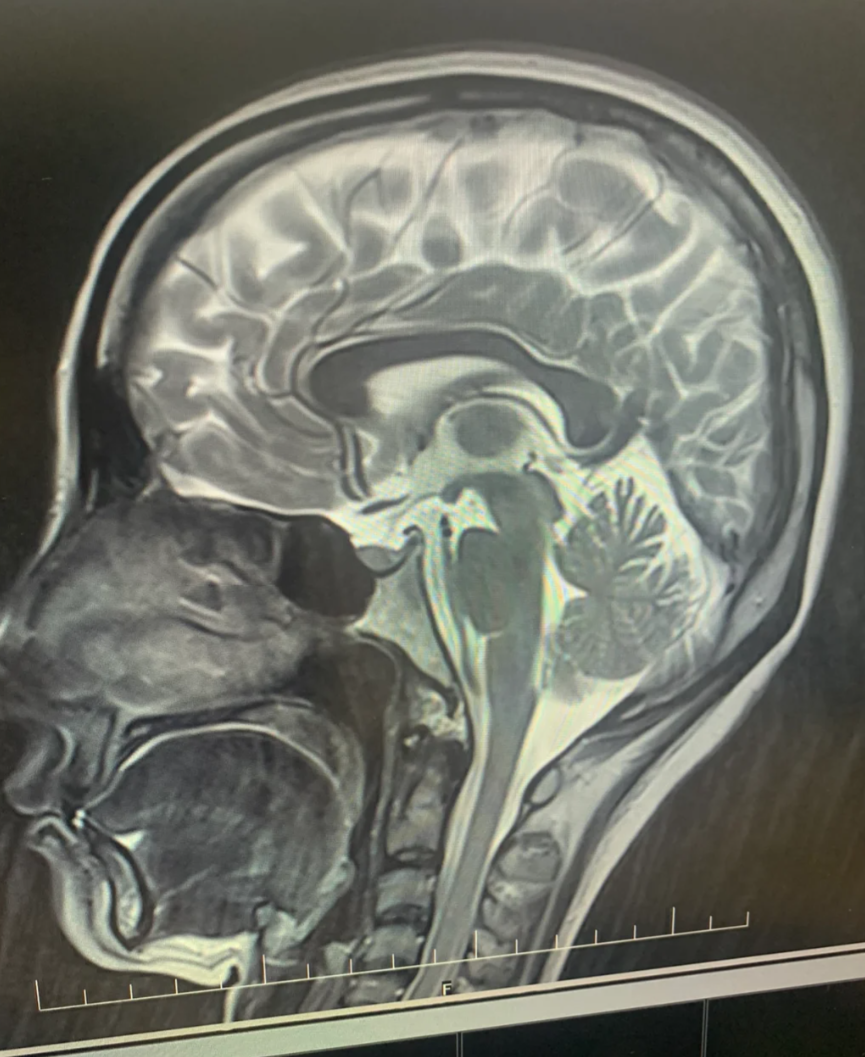

患者,女性,53,头疼头晕半年,本次mri垂体占位